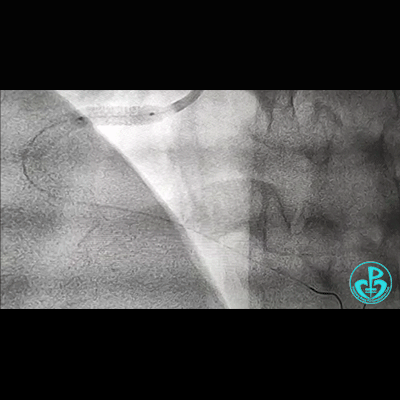

治疗过程

处理右冠,XB RCA,Sion、Sion blue导丝,2.0×20mm球囊。支架植入过程相当顺利,很快就完成,窃喜!心想后扩后马上结束!

植入3.5×29mm和3.5×24mm支架。